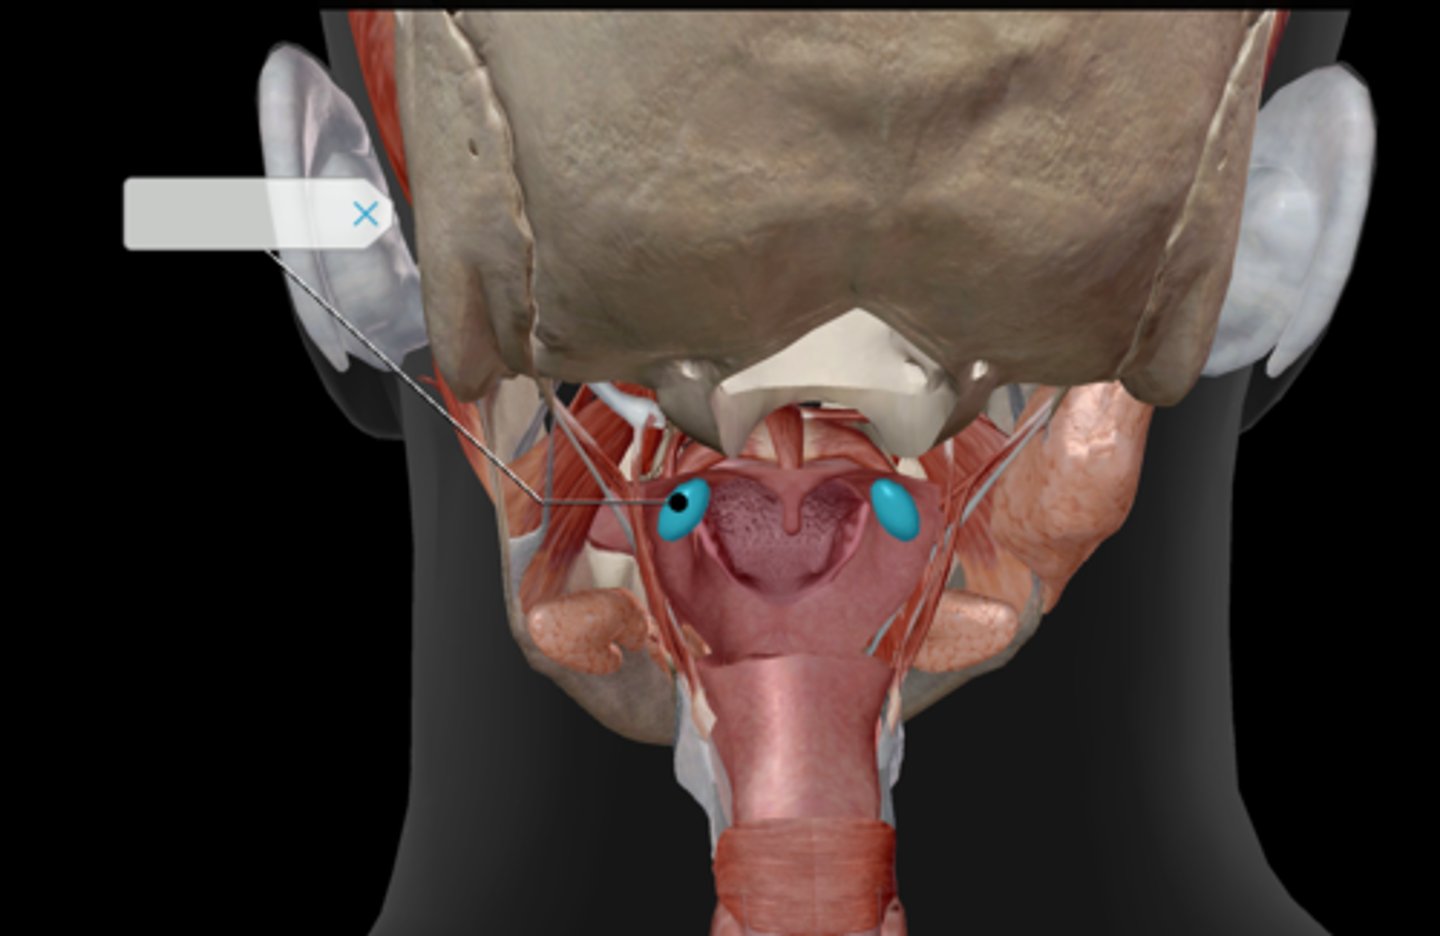

Epiglottis

Arytenoid cartilage

Corniculate cartilage

Vocal ligament

Vocal folds

Vestibular folds

Uvula